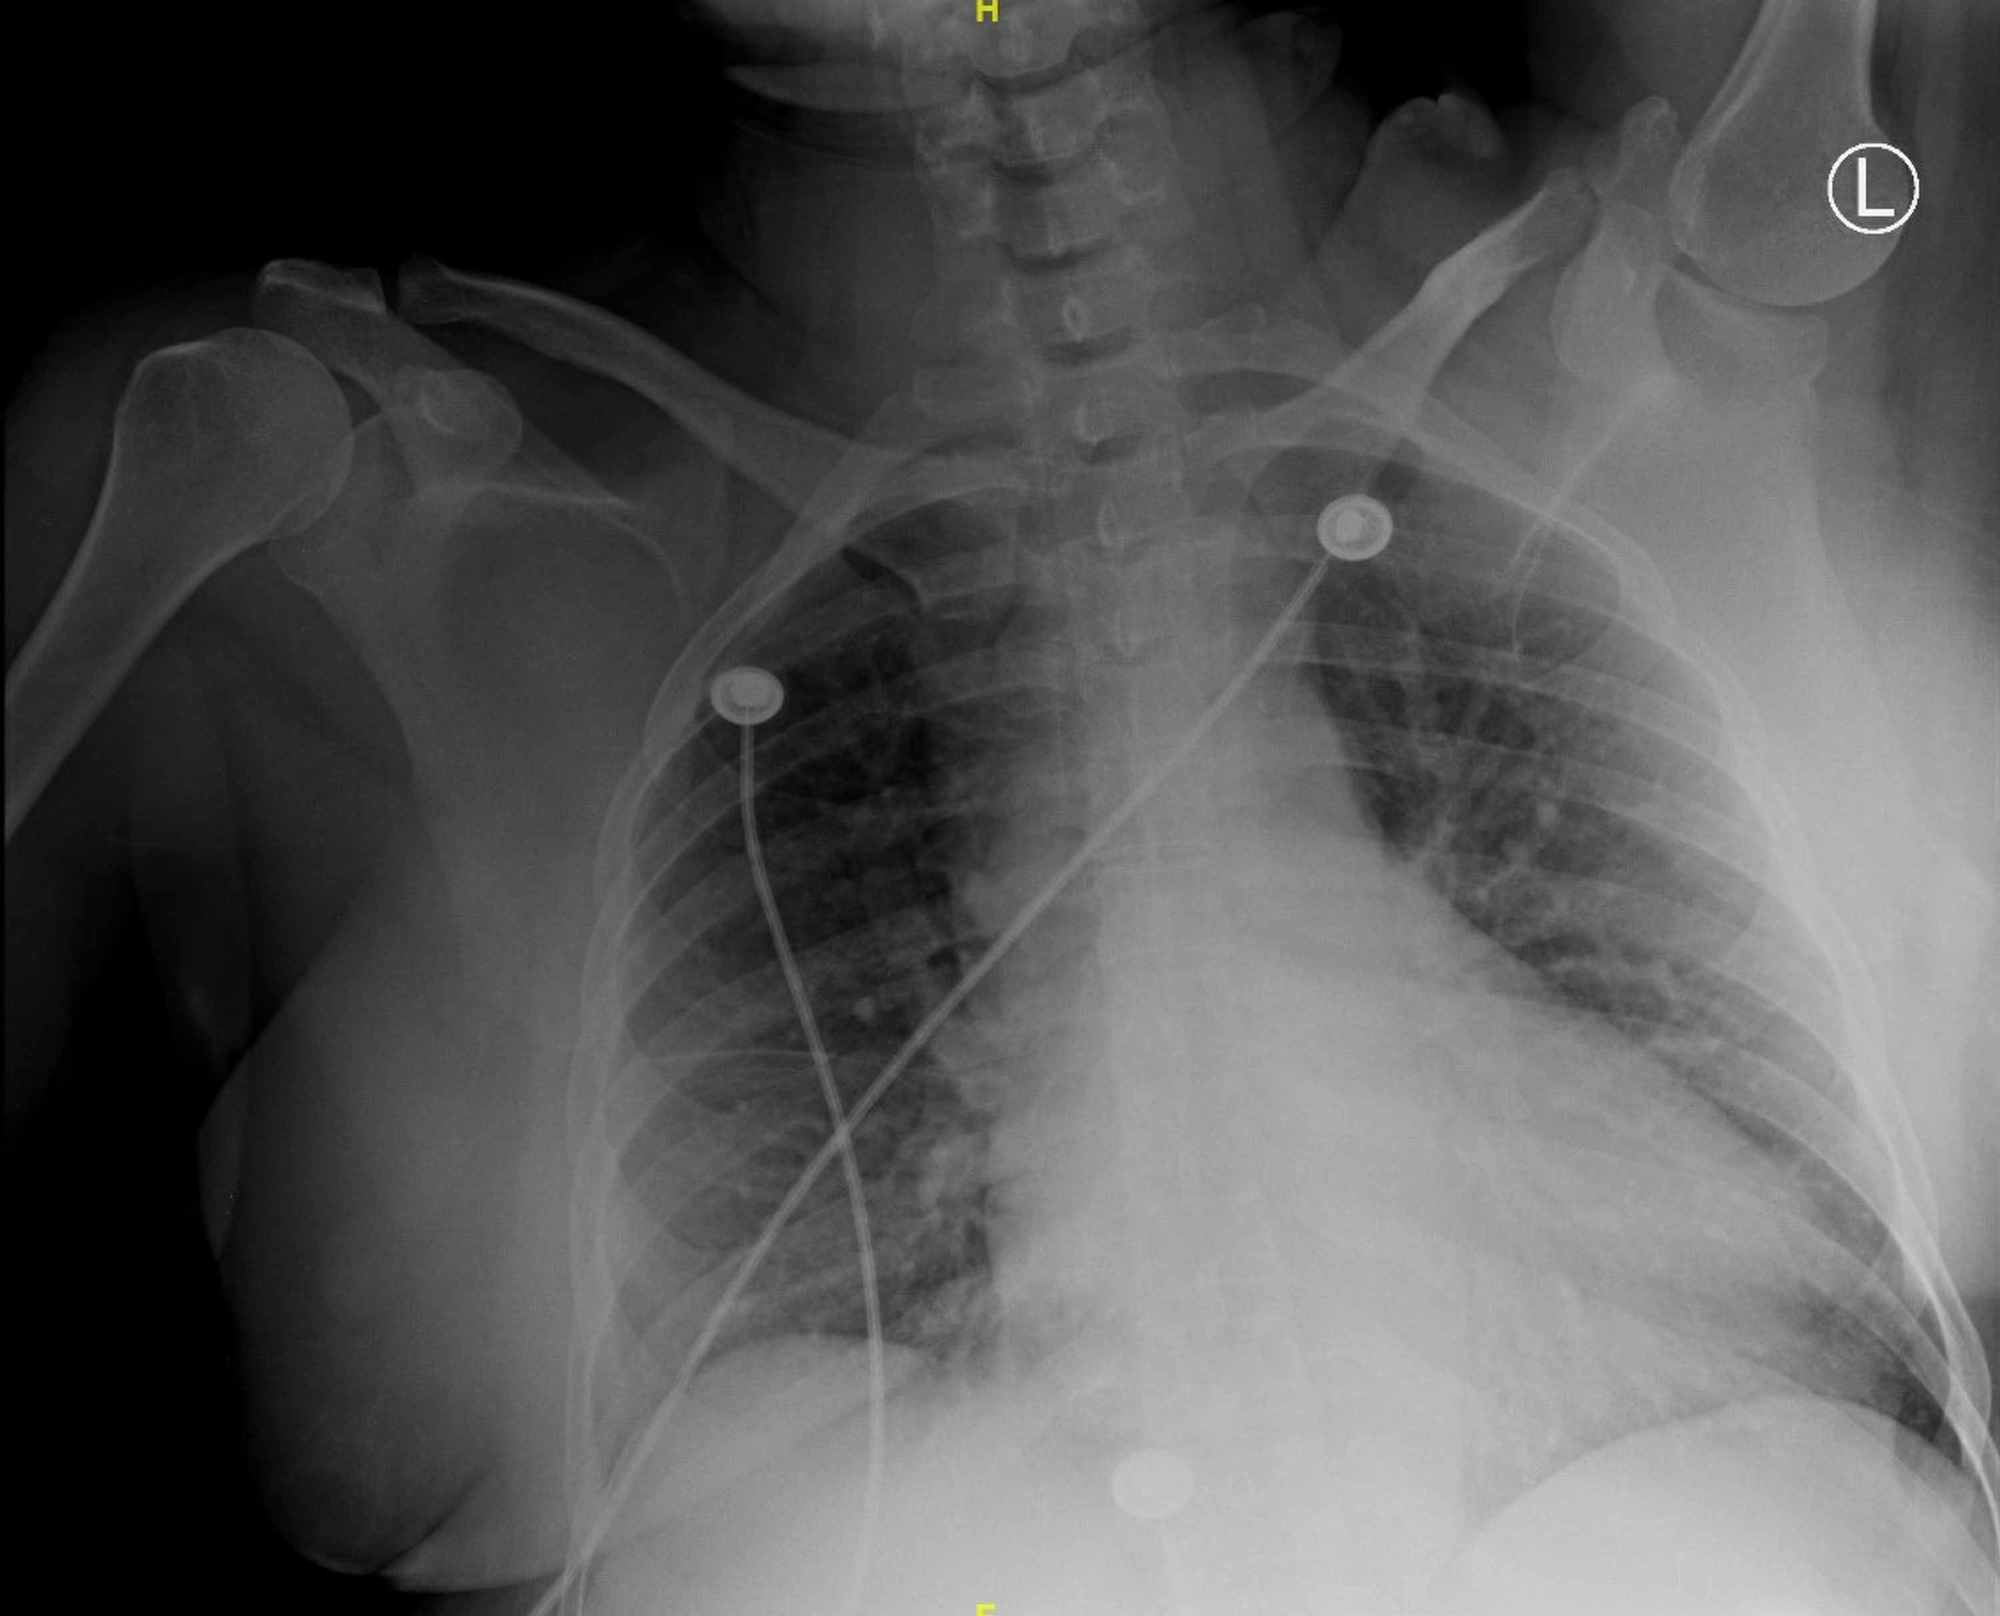

Chest X Ray Findings Myocardial Infarction . Reduced air entry, coarse crackles) to screen for. Respiratory distress, pallor, diaphoresis, tachycardia, high/low bp, s4 heart sound, signs of mitral regurgitation, pulmonary oedema. Features of myocardial infarction (e.g., chest pain, nausea, vomiting). Sound waves (ultrasound) create images of the moving heart. Patients may develop severe hypotension following nitroglycerine or morphine. Chest radiography is useful in determining the presence of cardiomegaly, pulmonary edema, pleural effusions, kerley b lines, and other criteria of hf. The traditional triad of findings seen in rvmi is hypotension, clear lung fields, and jugular venous distention. This test can show how blood moves through the heart and heart valves. An echocardiogram can help identify whether an area of your heart has been damaged.

Chest X Ray Findings Myocardial Infarction Chest radiography is useful in determining the presence of cardiomegaly, pulmonary edema, pleural effusions, kerley b lines, and other criteria of hf. Sound waves (ultrasound) create images of the moving heart. Features of myocardial infarction (e.g., chest pain, nausea, vomiting). Chest radiography is useful in determining the presence of cardiomegaly, pulmonary edema, pleural effusions, kerley b lines, and other criteria of hf. Respiratory distress, pallor, diaphoresis, tachycardia, high/low bp, s4 heart sound, signs of mitral regurgitation, pulmonary oedema. This test can show how blood moves through the heart and heart valves. Patients may develop severe hypotension following nitroglycerine or morphine. Reduced air entry, coarse crackles) to screen for. The traditional triad of findings seen in rvmi is hypotension, clear lung fields, and jugular venous distention. An echocardiogram can help identify whether an area of your heart has been damaged.